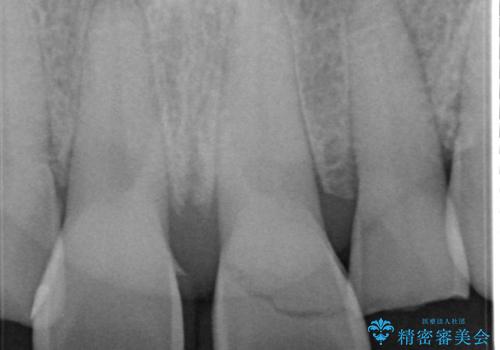

左上1が水平的に割れている状態で、歯冠を取り除くと神経が露出しており、唇側はかなり歯肉縁下で破折しており、そのままではかぶせものを入れるのは難しい状態でした。

抜かずになるべくその歯を残して使っていきたいとのことで、

根管治療をした上で歯を引っ張りだして(エクストリュージョン)、その後、骨外科にて歯周組織を整えた上で、かぶせものを入れていく治療計画をたてました。